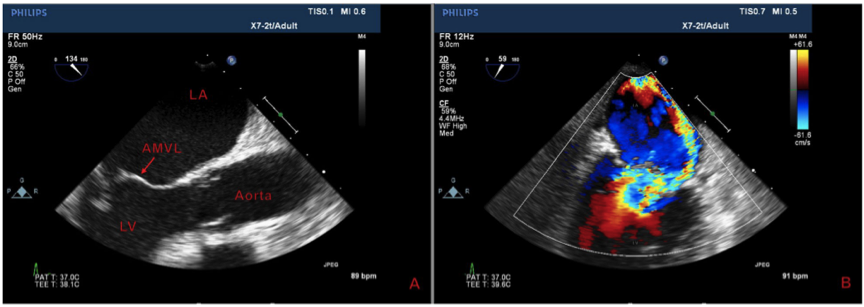

一名58岁男性,既往有慢性阻塞性肺病病史,因劳累而呼吸急促加重。其他主诉包括发烧,进展性咳嗽和心动过速。经鼻导管吸氧两升后血氧饱和度为96%,生命体征显著。经体格检查,患者没有明显的痛苦。胸部听诊啰音,心脏检查时心尖部最易听到的3/6收缩期杂音。血液检查中白细胞计数升高有重要意义。胸部X线检查与肺水肿一致。心导管检查显示非阻塞性冠状动脉疾病。经胸超声心动图(TTE)显示严重的二尖瓣返流,伴有后向偏心射流,后续经食管超声心动图显示二尖瓣前叶连枷状(AMVL)(图1)。

图1. 二尖瓣成像。(A)经食管超声心动图显示二尖瓣前瓣瓣叶连枷状,(B)经胸超声心动图显示后向返流射流(蓝色)